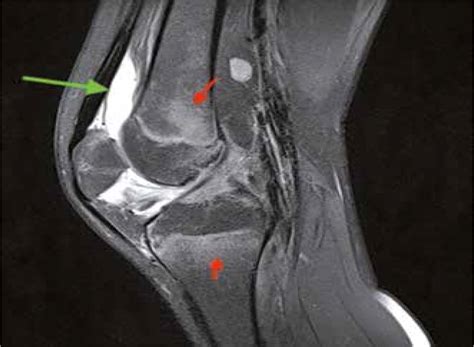

Interpreting knee MRI images is a skill reserved for radiologists, who analyze the scan and produce a detailed report for your referring physician. However, having a basic understanding of what they are looking for can help you better understand your diagnosis. Radiologists look for changes in signal intensity; healthy tissue typically appears in a predictable pattern, while injured or diseased tissue will show up as "brighter" or "darker" areas, known as signal abnormalities.

Meniscus Typically dark; bright signal within the meniscus often indicates a tear.

When you receive your results, the radiologist’s report will describe these findings in technical terms. For instance, they might describe a high-signal intensity within the meniscus, which suggests a possible tear, or they may note the presence of an effusion, which is an excess accumulation of fluid in the joint, often indicating inflammation or injury.